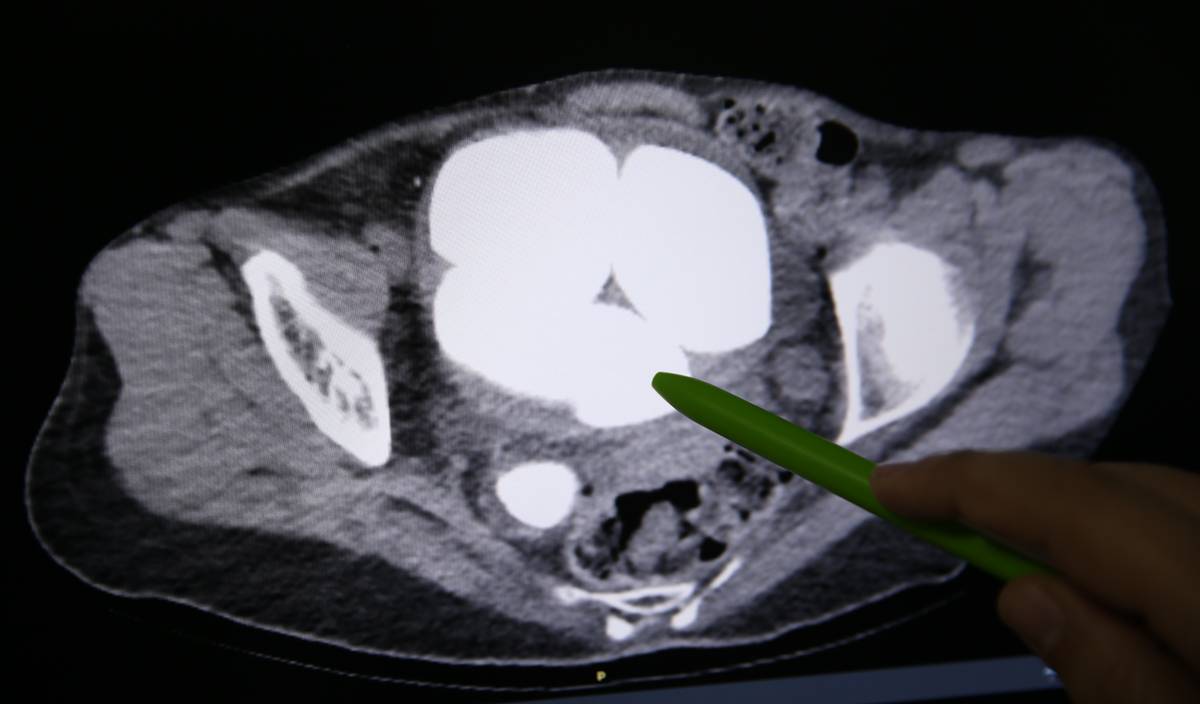

Üroloji Bölümünde Opr. Dr. Süleyman Çankaya tarafından yapılan tetkiklerde, hastanın mesanesi ve idrar kanalında en küçüğü 2, en büyüğü 9 santimetre olan 6 taş tespit edildi.

Çankaya ve Opr. Dr. Yekta Bıçak'ın geçen hafta gerçekleştirdiği cerrahi müdahale ile hastanın idrar kanalı ve mesanesinde bulunan farklı ebatlardaki 6 taş yaklaşık 1,5 saat süren operasyonla çıkarıldı.

Bazı taşlar işlem sırasında kırılırken, taşların yaklaşık yarım kilogram ağırlığında olduğu belirlendi.